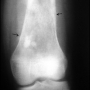

Osteoblastom

Daha nadir olarak görülen büyük bir osteoid osteomadır. En sık omurganın arka bölümünde ve uzun kemiklerin metafizinde ortaya çıkar. Ortadaki litik bölüm osteoid osteomada görülenden çok daha büyüktür ve etrafındaki skleroz çok daha incedir. İçindeki doku, osteoid osteomaya göre daha agresiftir. Omurgadaki ağrılı lezyonlar deformitelere (omurga eğriliğine) neden olabilirler. Tedavi bu bölgenin küretajı, tur aleti ile kazınması ve kemik dokusu ile doldurulmasıdır.